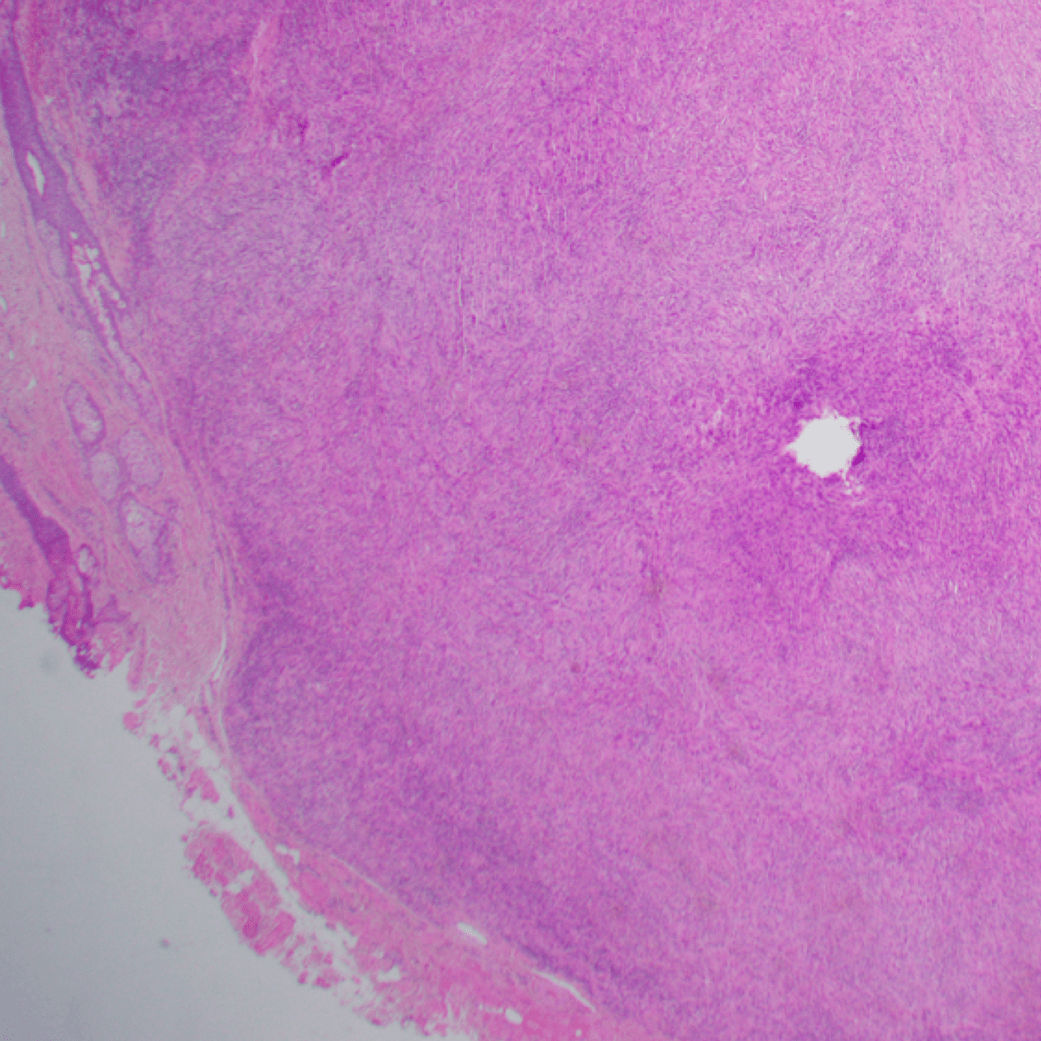

Case 2: Soft tissue lesion

Images

Diagnosis

Nodular Fasciitis

- Fibroblastic spindle cell proliferation

- Tissue culture-like growth pattern, bland nuclei

- Mitotic activity can be frequent (but not atypical)

- Variable cellularity

- Extracellular matrix ranges from myxoid to collagenous (older lesions may be more collagenous)

- Scattered lymphocytes, histiocytes, and osteoclast-type giant cells often present

- Areas of cystic degeneration may be identified

- Majority: MYH9::USP6 fusion; other fusion partners possible